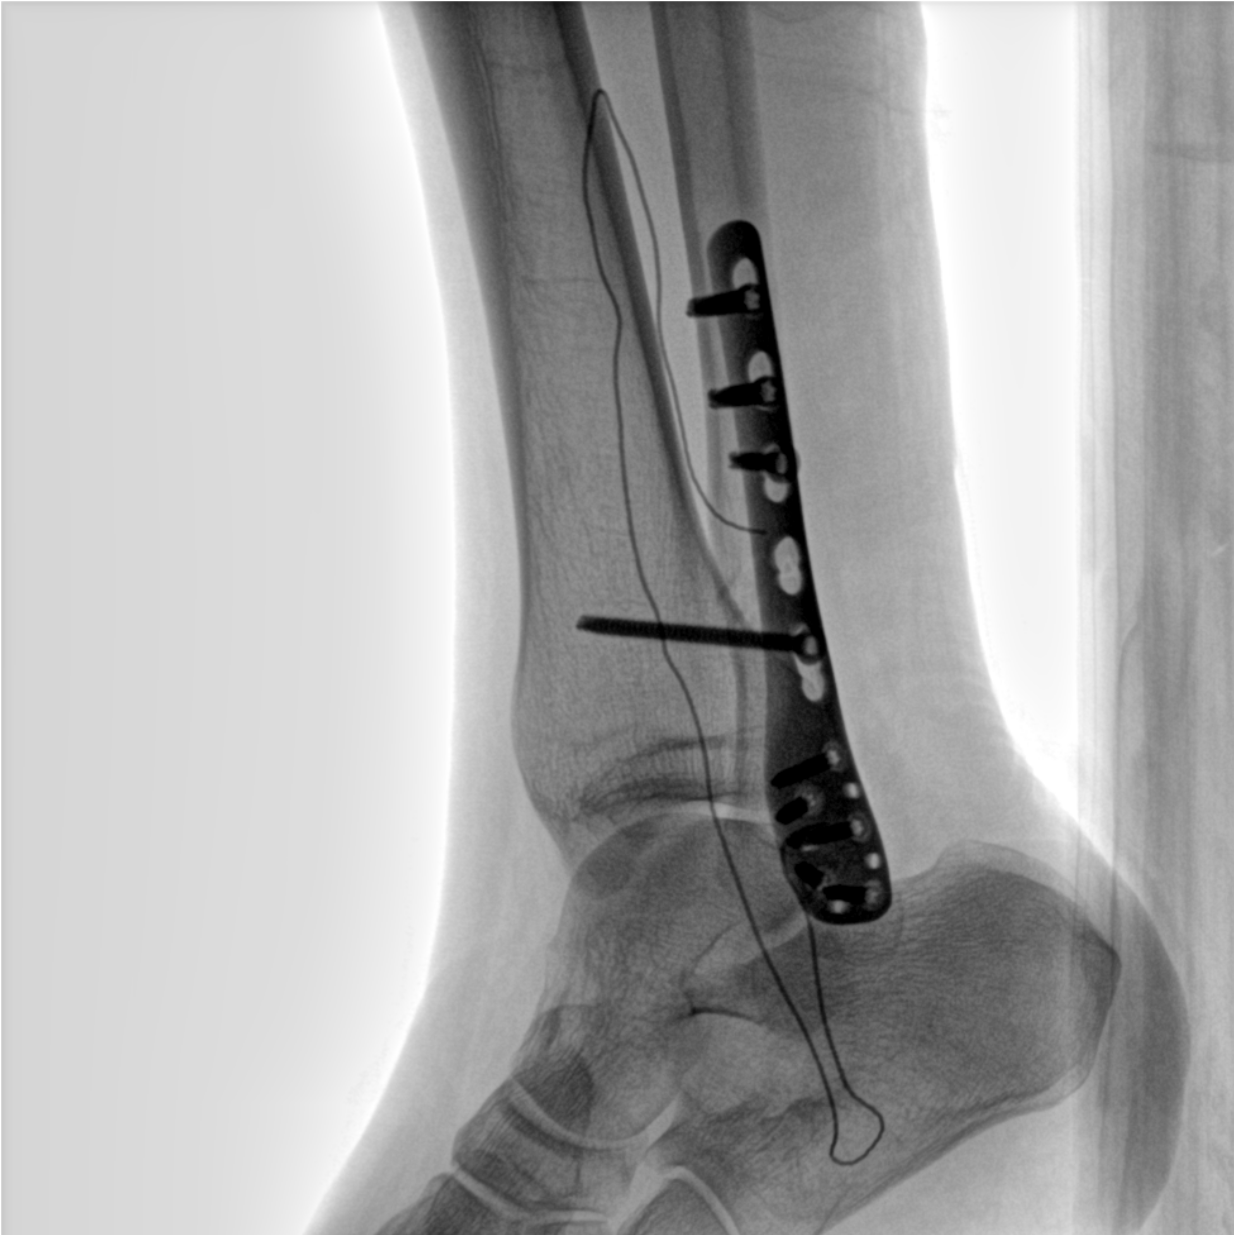

術(shù)中三維成像和橫斷面圖像提供多角度的手術(shù)診斷信息,輔助醫(yī)生進行術(shù)中評估判斷,諸如骨折復(fù)位情況和內(nèi)植入螺釘?shù)某叽绾臀恢?,輔助手術(shù)更好地完成。